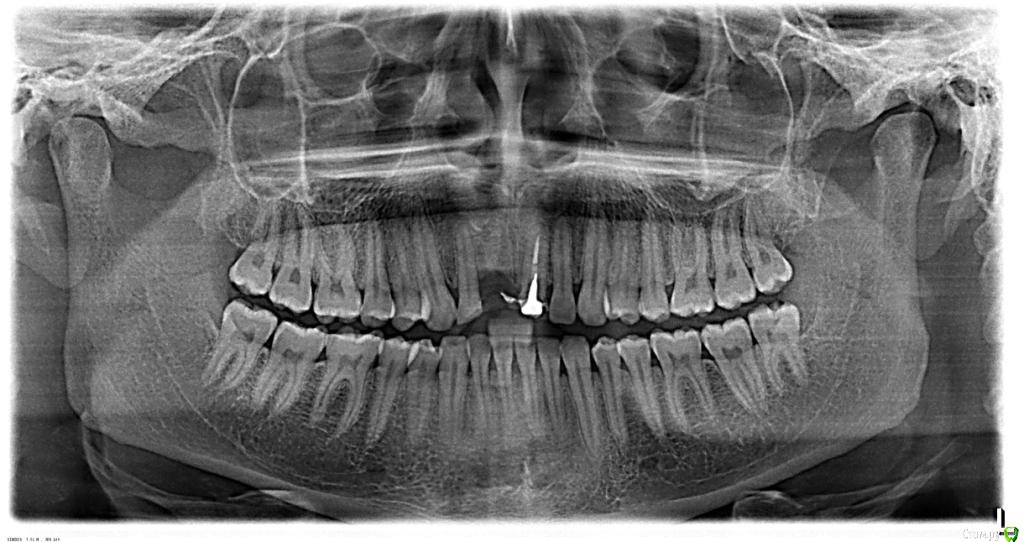

Здравствуйте, необходим свежий взгляд на мою проблему. С раннего детства в возрасте 7-8 лет получил травму, сломав два  верхних передних зуба (11, 21). У них были удалены нервы и запломбированы каналы, в возрасте 17-18 лет надеты постоянные, спаянные коронки. В возрасте 25 лет из-за полученной травмы (неудачного падения) был сломан корень 21 зуба, что привело к его удалению. На второй зуб (11) была установлена культевая вкладка и одета коронка. Через год после удаления решился на имплантацию утраченного зуба. Лечащий врач посоветовал нарастить кость для более правильной и надежной  установки импланта и возможности  дальнейшего протезирования с эстетической точки. Провели костную пластику, установлена была мембрана коллагеновая и подсыпан костный материал (не свой) под нее. То ли у меня отторжение этого материала произошло, то ли из-за недостаточного объема десны инфицировалась мембрана, так как оперирующий меня врач с трудом наложил операционные швы, ему пришлось натягивать десну за счет соответствующих надрезов ее у соседних зубов. Операция длилась около двух часов. Оказывается, у меня срослась десна с костью, или проросла в кость, из-за свича давнишнего, точно не знаю. После операции (3-4 дня) десна в области подсадки костного материала поменяла цвет и начала истончаться и провисать. Десна не заживала, и в месте подсадки костного материала просто рассосалась. Лечащий врач сказал мне, что все заживет со временем и посоветовал наносить пасту Солкосерил дентальный на поверхность дефекта.

post-41404-0-74323700-1418589126_thumb.jpg